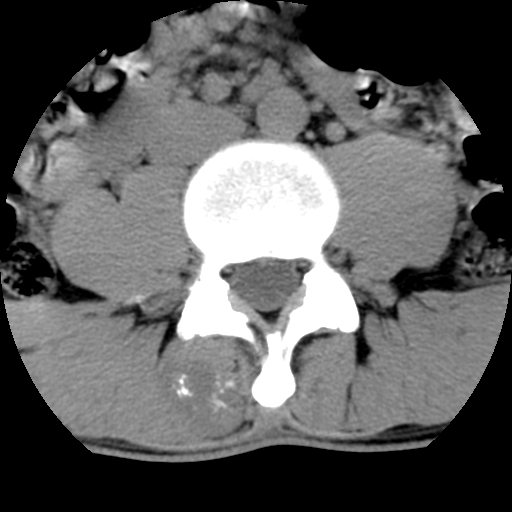

男,腰背痛

本人诊断1tb2包虫,请会诊

1)右侧竖脊肌稍低密度肿块伴钙化(性质待定),不排除肿瘤可能;建议行进一步检查。2)腰椎间盘突出。

考神经源性肿瘤可能性,不除外结核,建议增强.椎间盘突出

1.右侧竖脊肌软组织肿块伴团块状钙化,首先考虑血管瘤可能性大;建议行进一步检查;2。腰椎间盘突出。

软骨肉瘤可能性大